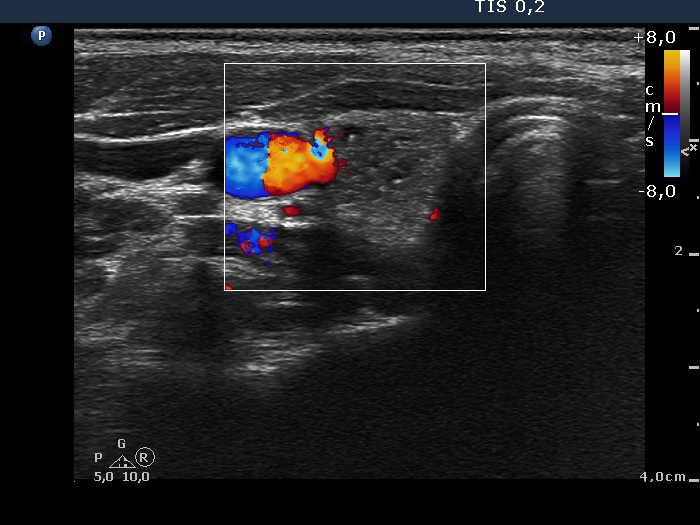

Ultrasonography: The thyroid was echonormal. There was a moderately hypoechogenic inhomogeneous nodule in the lower pole of the right lobe. There were two lymph nodes next to each other above the right thyroid in the submandibular area. The lymph nodes presented a regular hilum.

This is the typical presentation of a bacterially infected lymph node. In most of these cases we find multiple lymph nodes next or very close to each other. The presence of ill-defined hypoechogenic areas within the lymph nodes is an even more important sign of a bacterial lymphadenitis.